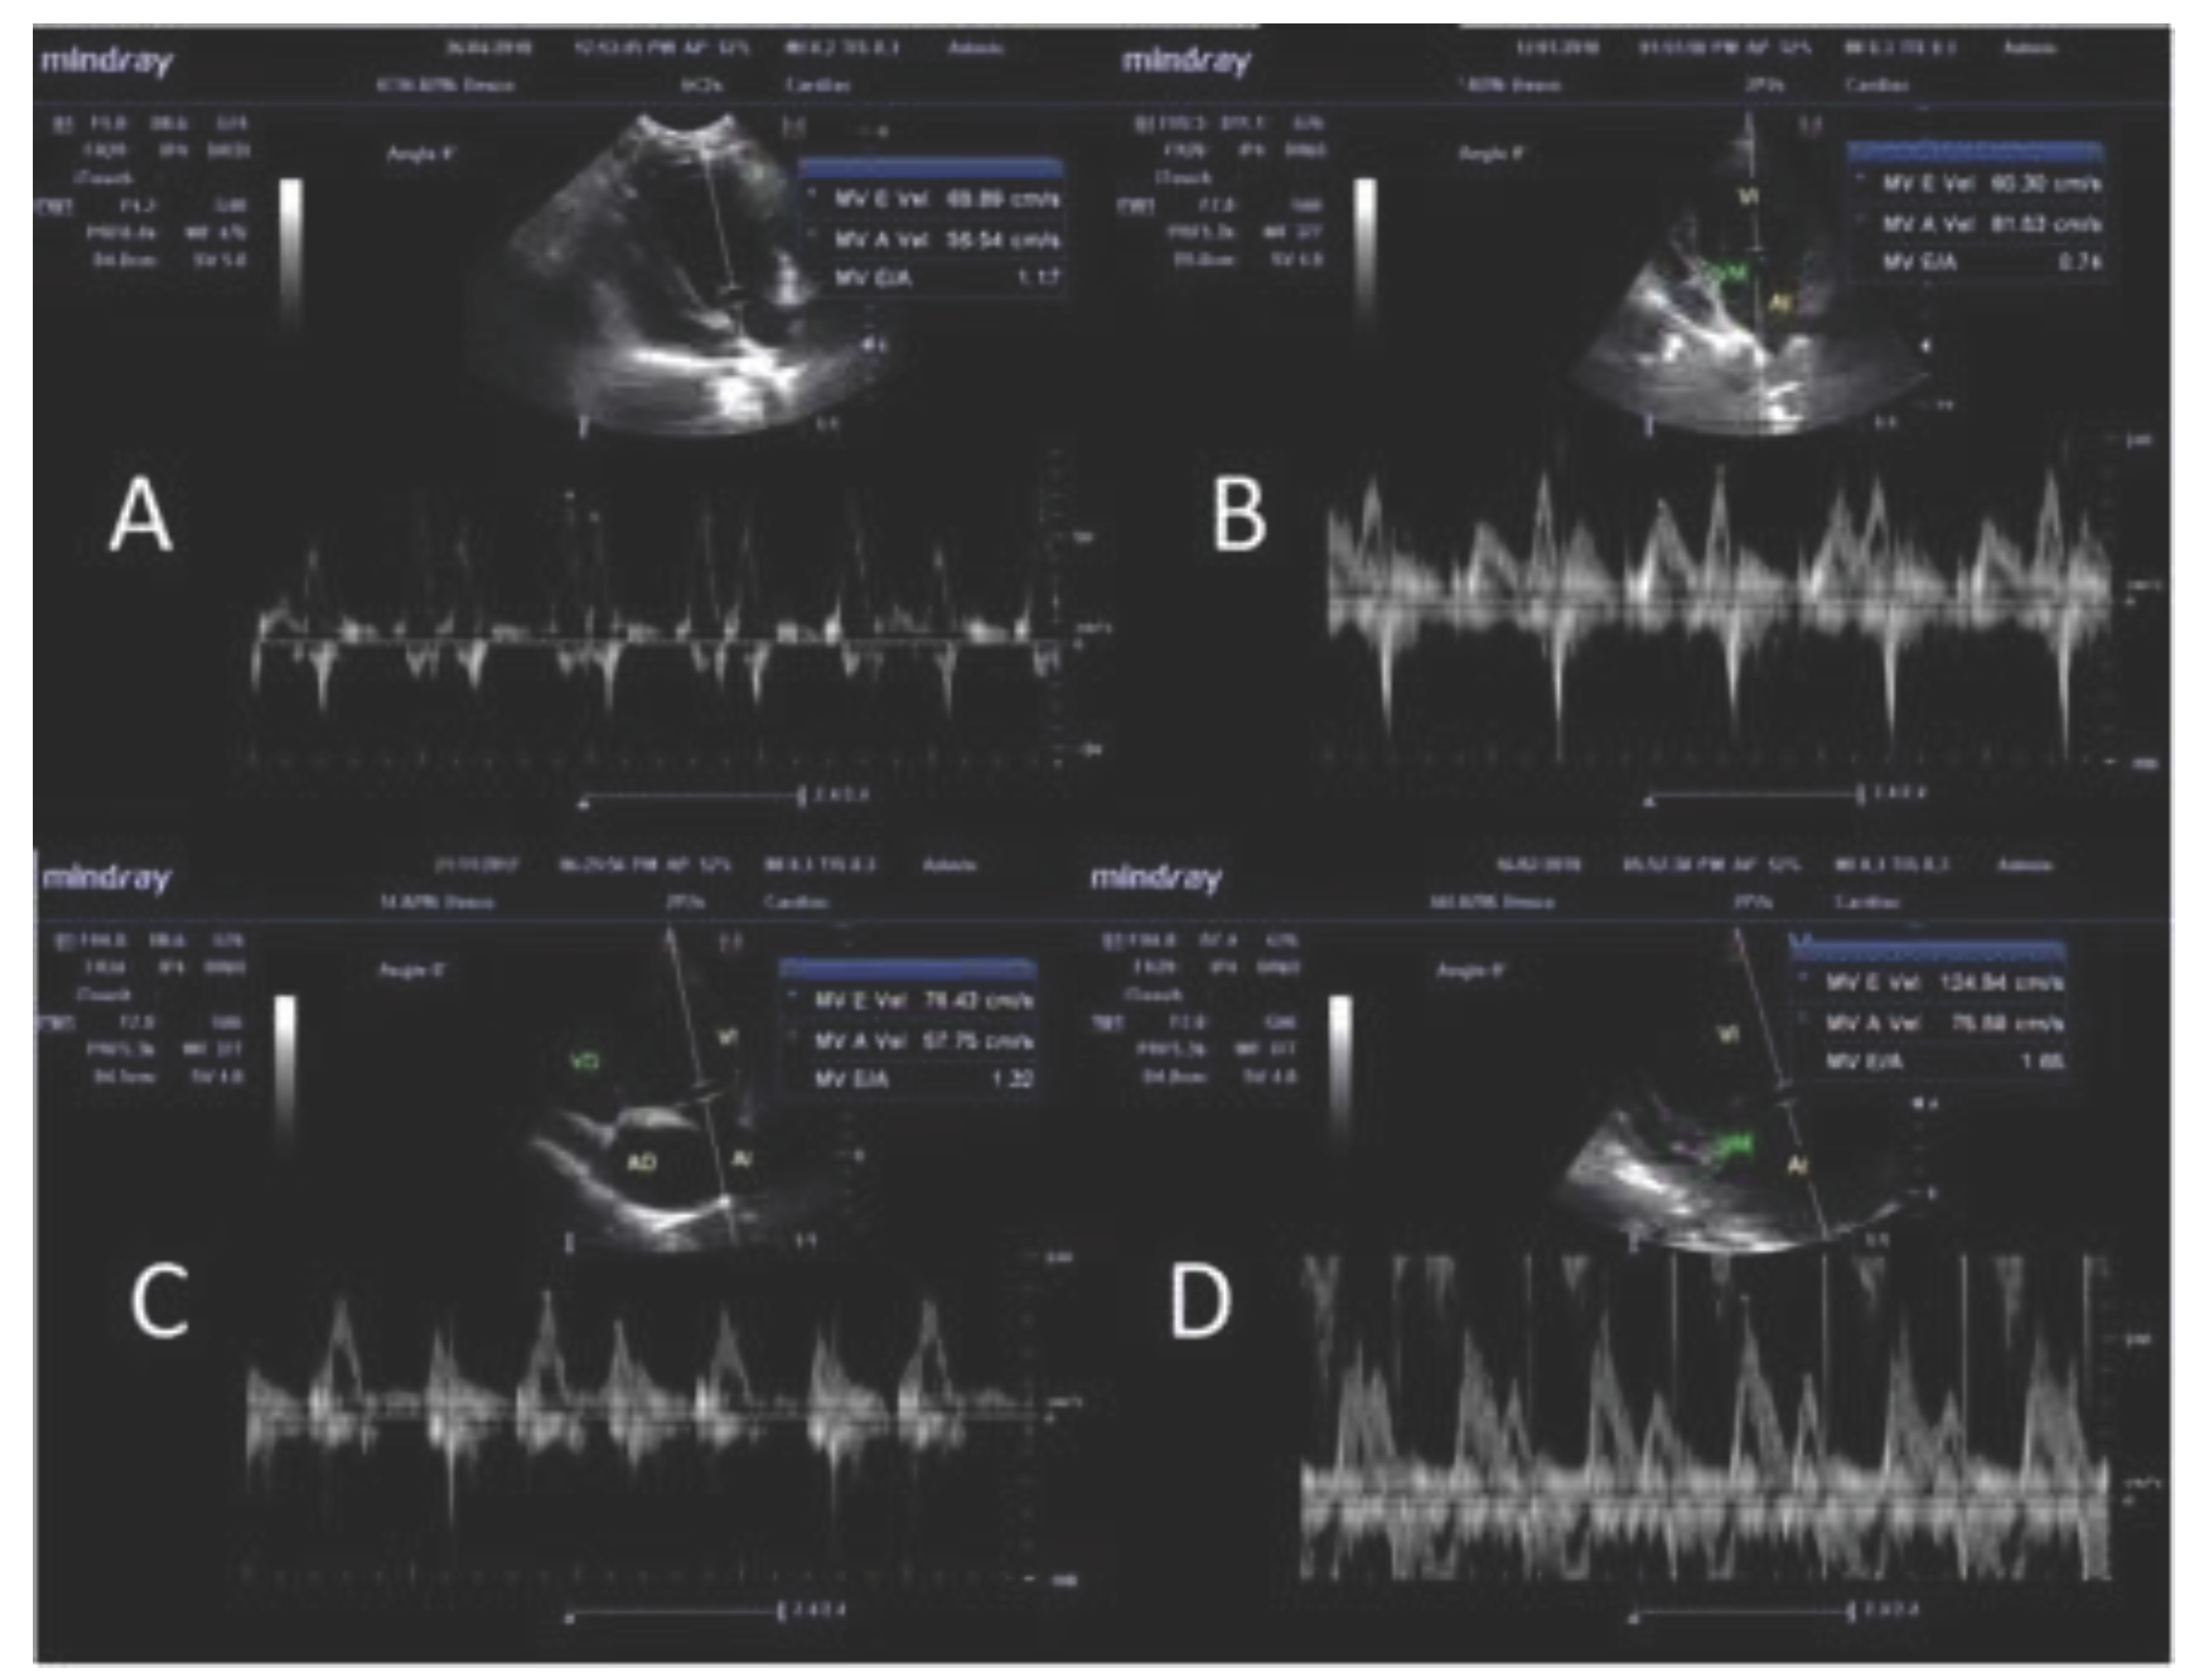

3.4. Pulse Doppler Ultrasonographic Findings

| E/A ratio 1 | PW Doppler | 1.53 ± 0.34 a | 1.24 ± 0.24 | 1.35 ± 0.26 | 1.37 ± 0.34 | 1.41 ± 0.61 | 1.1 ± 0.29 a |

| Parameters | Mode | A (n=23) | B (n=6) | C (n=85) | Reference value | |||

| E/A ratio | PW Doppler | 26.09 | 8.70 | 16.67 | … | 11.76 | 3.53 | 0.98 - 1.7 4 |